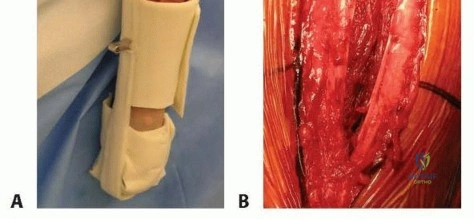

While conservative management with a prefabricated functional fracture brace remains the standard of care for many isolated, closed humeral shaft fractures, there are several absolute and relative indications for surgical intervention. Operative management requires extensive dissection and advanced operative skill but provides immediate stability, facilitates early mobilization, and simplifies nursing care in polytraumatized patients.

Positioning and Room Setup

For the anterolateral approach, the patient is placed in the supine position on a radiolucent operating table. A radiolucent arm board is attached to the operative side. The patient is positioned close to the edge of the table to allow the shoulder to drop posteriorly, facilitating access to the lateral aspect of the arm.

A sterile tourniquet may be placed high on the brachium, though it is rarely inflated due to the proximal extent of most incisions and the robust vascularity of the arm which can typically be managed with electrocautery. The entire forequarter, from the base of the neck to the fingertips, is prepped and draped free to allow for full manipulation of the extremity and intraoperative assessment of elbow and shoulder range of motion. The C-arm fluoroscopy unit is brought in from the contralateral side or from the head of the bed, ensuring unimpeded orthogonal views of the entire humerus.

To safely exploit this interval, the fascia between the brachialis and brachioradialis is carefully incised. The radial nerve must be actively identified and protected. It is often easiest to identify the nerve distally where the interval is wider and trace it proximally to where it pierces the septum. Once identified, the nerve is gently mobilized and protected with vessel loops. Retraction of the nerve must be minimal and meticulous to prevent iatrogenic neuropraxia.